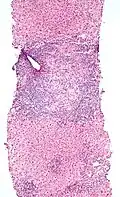

Mikrofoto einer primär biliären Zirrhose (HE-Färbung, mittlere Vergrößerung). -

Mikrofoto einer primär biliären Zirrhose (HE-Färbung, niedrige Vergrößerung).